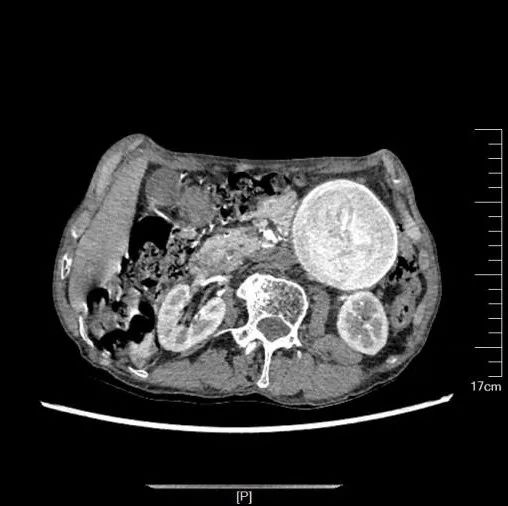

患者因出现左胸腹部疼痛至当地县医院就诊,提示腹主动脉瘤,后转至市人民医院就诊,急诊收住肝胆胰外科二病区(血管外科、介入科)。肝胆胰外科团队为其完善相关检查,其中胸腹部CTA检查提示:腹主动脉下段可见巨大瘤样扩张,直径约75mm,双侧髂总动脉管腔扩张。

腹主动脉瘤体巨大、瘤颈较短,手术难度大,在术前充分研讨、准备后,科室特邀专家工作站专家云南省第一人民医院血管外科龚昆梅主任现场指导手术。

手术采取“腹主动脉瘤切除+人工血管置换术”的方式,通过全麻下开腹暴露腹主动脉瘤,阻断病变段主动脉血流后切除瘤体,用人工血管与正常血管断端吻合,重建血流通道。